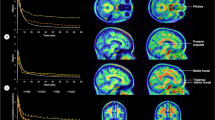

Since BSO and SM groups were both experiencing 17β-estradiol loss, we next focused on the differences and similarities between the two different menopause types, BSO and SM, asking whether whole-brain function and hippocampal connectivity after BSO were similar or different from that observed in older women in SM. To assess whole-brain function during Novel and Repeat conditions, we used multivariate PLS. We found one significant latent variable (LV1: p=0.008, percent cross-block covariance accounted for 98.25%; Table 2; Fig. 5). The BSO and SM groups showed similar patterns of activity, with increased activity in right middle frontal gyrus and left posterior cingulum—negative salience regions—during encoding of Novel face-name pairs and increased activity in left hippocampus, inferior and middle temporal gyri, inferior frontal gyrus, bilateral rectus gyri, and cerebellum—positive salience regions—during encoding of Repeat pairs. BSO+ERT differed significantly from BSO and SM, showing the opposite pattern, i.e., increased activity in left hippocampus and temporal regions during encoding of Novel face-name pairs and increased activity in frontal and cingulate cortices during encoding of Repeat face-name pairs.

Latent variable 1 (LV1) from task Partial Least Squares: a) Spatial maps depict highlighted regions for LV1; p=0.008, percent cross-block covariance accounted for 98.25%; b) Bootstrap distribution profile for LV1 with 95% confidence intervals; a pattern of Novel and Repeat face-name pair encoding-related activity was significantly different for BSO+ERT compared to BSO and SM; BSO bilateral salpingo-oophorectomy, BSO+ERT bilateral salpingo-oophorectomy with 17β-estradiol replacement therapy, SM spontaneous menopause

Using PLS, we next focused on functional connectivity between the left and right anterior and posterior hippocampi of BSO, BSO+ERT, and SM. When we calculated HRF-weighted correlations between four regions within the left and right anterior and posterior hippocampius across Novel and Repeat conditions (Fig. 6a), we found that LV1 explained 72.91% of data variance and trended toward statistical significance (p=0.07). Thus, we examined LV1 further to identify differences in hippocampal connectivity. During Novel encoding, compared to Repeat encoding, BSO showed significantly decreased connectivity between left and right and left anterior hippocampi as well as between left anterior and posterior hippocampus (Fig. 6). In contrast, SM showed increased connectivity between left and right anterior hippocampi as well as between left anterior and posterior hippocampus during Novel encoding compared to Repeat encoding. These opposing connectivity patterns suggest that menopause type may influence functional connectivity within the hippocampus during associative encoding. BSO+ERT did not contribute to this latent pattern of effects: i.e., BSO+ERT did not recruit different hippocampal connections between Novel and Repeat conditions.

LV1 connectivity partial least squares: a) Connectivity between hippocampal regions with significant bootstrap ratios (BSRs) for LV1; p=0.07, percent cross-block covariance accounted for 72.91%; b) Brain score profile for LV1 with 95% confidence intervals; a pattern of Novel and Repeat face-name pair encoding-related connectivity was significantly different for BSO compared to SM; c) Group mean Fisher’s z-transformed correlation coefficients between left and right anterior hippocampal ROIs; d) Group mean Fisher’s z-transformed correlation coefficients between left anterior and posterior hippocampal regions; error bars represent standard error of the mean; BSO bilateral salpingo-oophorectomy, BSO+ERT bilateral salpingo-oophorectomy with 17β-estradiol replacement therapy, SM spontaneous menopause